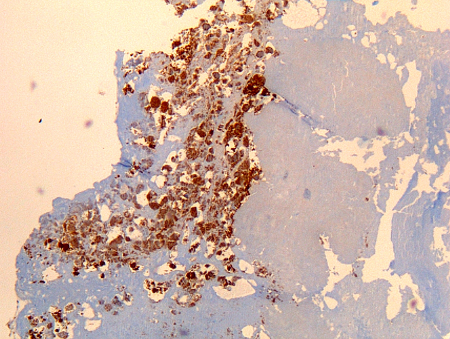

immunohistochemistry

Test

Considered a gold standard test for Coxiella burnetii, but is performed only in specialist laboratories.

Immunohistochemistry has the advantage of being able to identify bacterial infection in different cell types, but is not as sensitive as fluorescence in situ hybridisation (FISH).[Figure caption and citation for the preceding image starts]: Coxiella burnetii osteitis: immunohistochemistry: brown coloration identifies bacteria in monocytes/macrophages Hubert Lepidi, Institut Hospitalo-Universitaire Méditerranée Infection [Citation ends].

[Figure caption and citation for the preceding image starts]: Coxiella burnetii lung fibrosis: immunohistochemistry; brown coloration identifies bacteria in monocytes/macrophages Hubert Lepidi, Institut Hospitalo-Universitaire Méditerranée Infection [Citation ends].

[Figure caption and citation for the preceding image starts]: Coxiella burnetii endocarditis: immunohistochemistry. Note the low level of inflammation. Brown coloration identifies bacteria in monocytes/macrophages inside. Vegetation is usually lacking Hubert Lepidi, Institut Hospitalo-Universitaire Méditerranée Infection [Citation ends].

[Figure caption and citation for the preceding image starts]: Coxiella burnetii chronic lymphadenitis: immunohistochemistry. Note the isolated infected cell (monocytes/macrophages) in the lymph node. Brown coloration identifies bacteria in monocytes/macrophages Hubert Lepidi, Institut Hospitalo-Universitaire Méditerranée Infection [Citation ends].

[Figure caption and citation for the preceding image starts]: Coxiella burnetii chronic hepatitis of a patient with endocarditis: immunohiostochemistry. Note the absence of doughnut granuloma seen in acute Q fever. Brown coloration identifies bacteria in monocytes/macrophages Hubert Lepidi, Institut Hospitalo-Universitaire Méditerranée Infection [Citation ends].